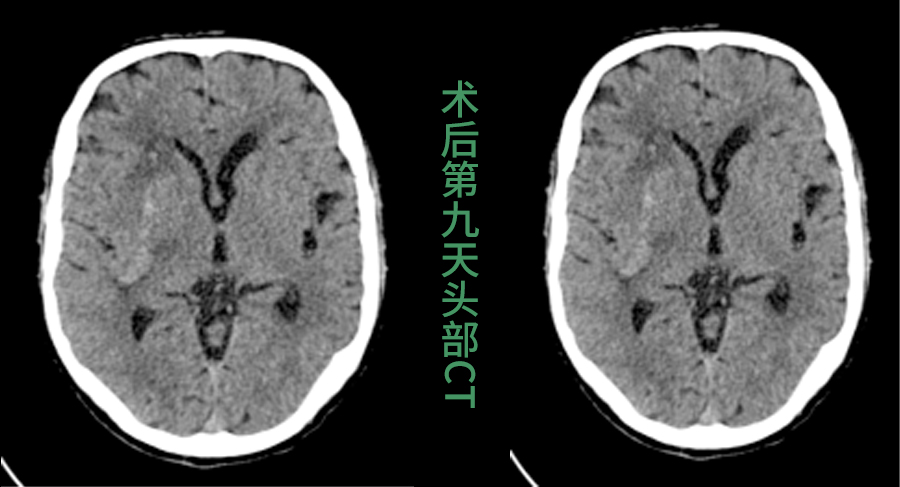

3.精准引导,一击即中:手术中,这枚特殊的“GPS”导板稳固贴合在患者头部,为手术穿刺针提供精确的进针角度和深度通道,穿刺导管沿此通道进入,直达血肿中心,实现毫米级的精准定位。